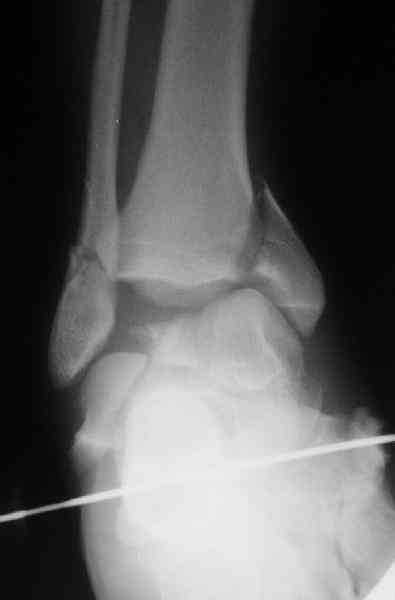

повторили рентгенограммы и доделали проекции, к единому мнению все еще не пришли

На ренгенограмме не уловил многоскольчатость тарана, чтобы доказать, конечно, можно было исследовать на КТ, потом КТ дает ориентацию фрагментов.

Два фрагмента суставной поверхности тарана можно восстановить боковой компрессией шурупами и дополнительно костная пластика.